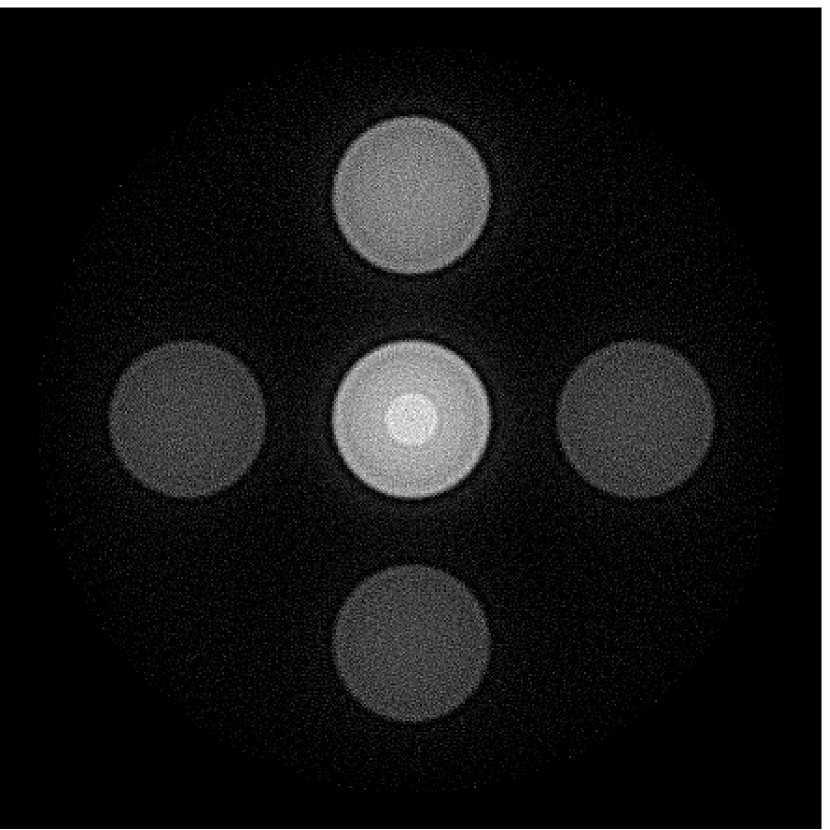

The images and EIRs reconstructed by use of the VP algorithm that was based on the 2D imaging model that neglected the SIR are shown in Figures 15 and 16. The latter figure contains results corresponding to different values for the regularization parameter . From Fig. 15, it can be observed that use of the conventional iterative method that utilized the measured EIR resulted in distortions and loss of details in the reconstructed images. Use of the VP algorithm improved the contrast and the details in the reconstructed images (Fig. 15(c) and 16(a)). Furthermore, the images reconstructed by use of the VP algorithm had a more uniform background.

In Figure 17, the results corresponding to use of the 3D imaging model that incorporated SIR effects are shown. The EIR estimated by the VP algorithm is also shown. In Figure 18, images and EIRs reconstructed by use of the VP algorithm with different regularization parameters values are shown.

Similar to the case described above where the transducer SIR was neglected, these results reveal that use of the VP algorithm can produce images with a cleaner background and enhanced spatial resolution than yielded by use of a conventional iterative algorithm that employed the measured EIR. For example, detailed information regarding the vessels near the organ’s periphery was better preserved by the VP algorithm than by the conventional iterative algorithm. These images corroborate our assertion that the VP algorithm can significantly reduce the artifacts and distortions in the reconstructed image. It is also worth pointing out that, unlike the numerical phantom studies, the artifacts and distortions in the images may be caused not only by the inaccurate EIR but also by other factors, such as neglecting acoustic heterogeneities and the variation of the EIRs among the elements of the transducer array. In such cases, the EIR estimated by the VP algorithm represents an effective system impulse response that minimizes the inconsistency between the measured data and the imaging model.